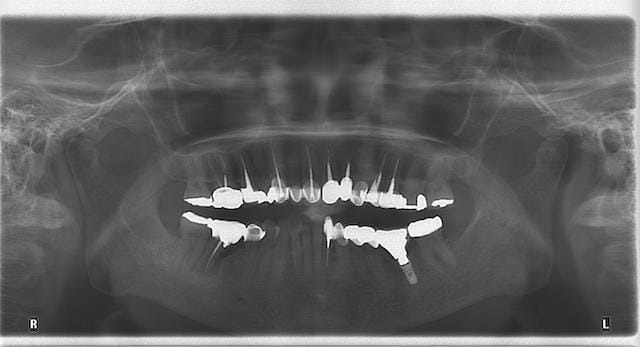

圖示:由Mrs.Hsieh的全口X光片中,也可看出口內有多顆假牙,且多顆牙齒做過根管治療

從全口的照片也可以發現,她因為蛀牙率很高,早期看牙的經歷很多,口內有將近20顆假牙,並且很多顆牙齒做了根管治療。

她之前有全口中度牙周病,治療過後都有好好地定期維護,因此多年來牙周都能維持穩定且延緩惡化。